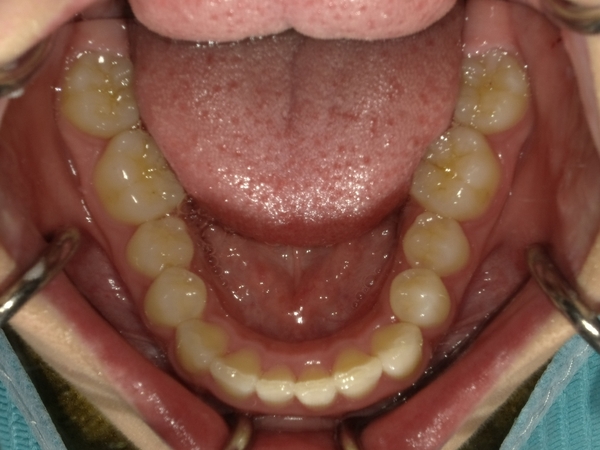

ガタガタとした歯並びや八重歯(叢生)CASE51